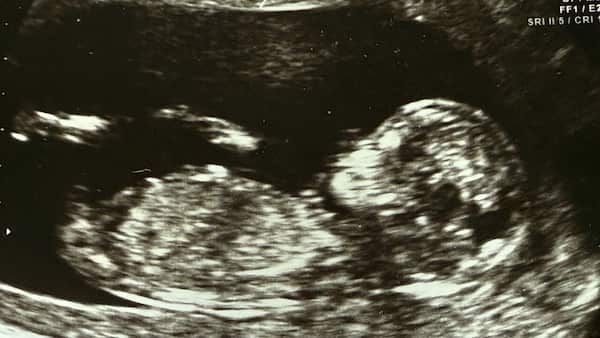

Thousands of pregnancies in Australia each year are conceived using assisted reproductive technologies. Source: Shutterstock, The Conversation / Lee Charlie